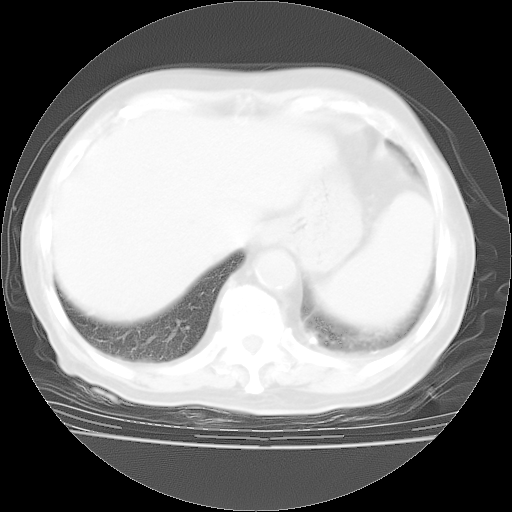

今天部分检查

轻微咳嗽,无痰,(体温正常时)R20次/分,P75次/分,双肺底、腋下可闻及少量捻发音。下肢轻度浮肿。

血常规:白细胞9.11×109/L,N0.92,L5.64,血小板39.2×109/L,HB148g/L,ESR2mm/H。

尿常规:潜血+

血生化:总蛋白69.71g/L,白蛋白38.40g/L,球蛋白31.31g/L,CRP27.9mg/L,尿素氮11.98mmol/L,肌酐106μmol/L,乳酸脱氢酶1099 U/L,肌酸激酶108U/L,CK-MB 61U/L。

腹部B超:胆囊壁增厚,肝、胆、胰、脾、肾无异常,肠系膜淋巴结、腹膜后淋巴结无增大。

ECG:右心室增大

心脏超声检查:无右心室增大。

增加治疗:异烟肼、利福平、乙胺丁醇,静滴左氧氟沙星、参麦注射液。甲强龙从80mg暂减为40mg。

强的松3月1日改为10mg qd,4月1日改为10mg qod。3月份以前的减量过程和环磷酰胺疗程需等明天查看记录(我岳父自己做的记录在他家里)。